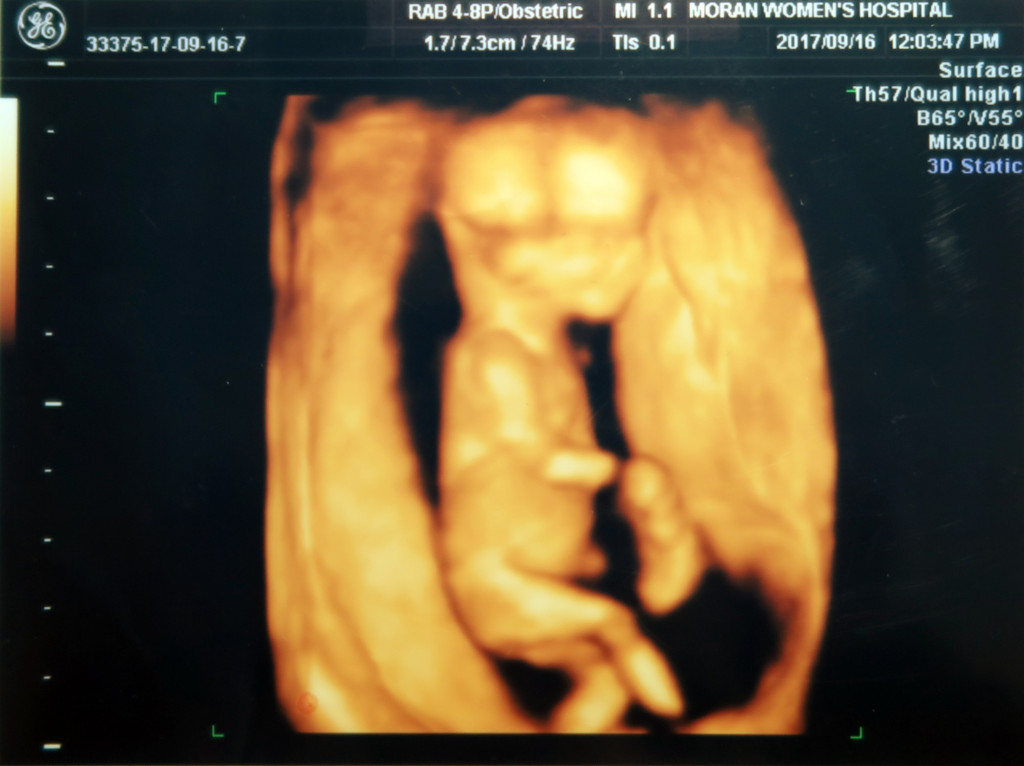

1차 정밀초음파 때 (13주) 아빠의 매의눈은 봐 버렸습니다 ( ◥◣_◢◤ )

달이 다리 사이에 무언가 있는것을ㅎㅎ

선생님께 재차 무언가 있는 것이냐 물었지만 선생님은 대답이 없으셨어요ㅋㅋ

재차 삼차 묻는 제가 불편하셨는지 선생님의 눈빛은 흔들리고 ㅋㅋㅋ 그 부위 근처만 가면 다른 곳으로 옮기시던 선생님 (◎-◎;)